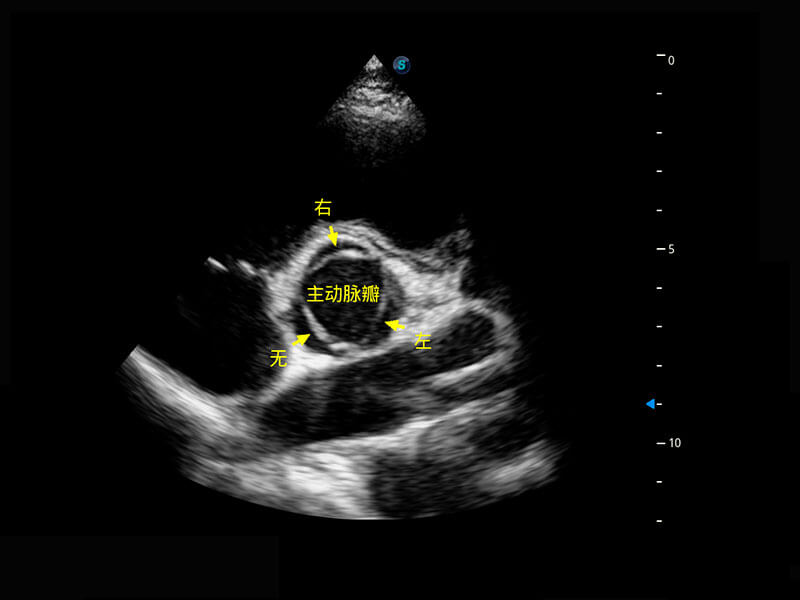

P60搭载一系列胎儿心脏成像技术,实现精细的胎儿心脏评估。

右室双出口